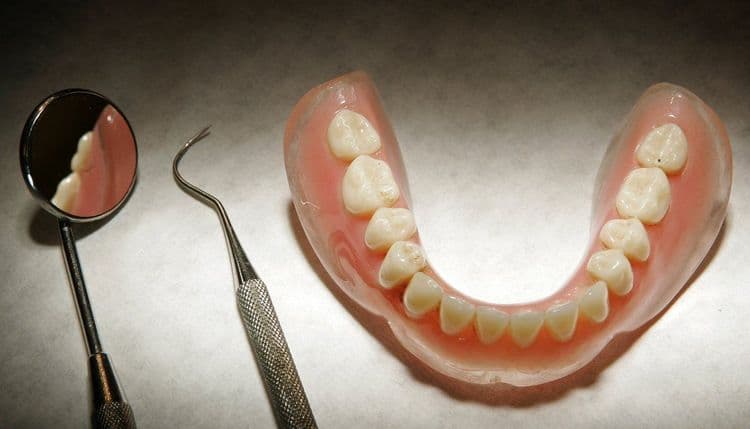

हे जेव्हा आजोबांना सांगण्यात आलं तेव्हा ते म्हणाले की माझी कवळी ऑपरेशनपासून हरवली आहे. हे समजताच त्यांच्या घशाचा एक्स-रे काढण्यात आला. यावेळच्या एक्स-रे मध्ये त्यांची हरवलेली कवळी त्याच्या घशात अडकल्याचं उघड झालं.

मंडळी, शस्त्रक्रियेच्या वेळी अनेस्थेशिया दिल्यानंतर त्यांची कवळी त्याच्या घशात पडली आणि त्यांने ती नकळत गिळली होती. आजोबांवर तातडीची शस्त्रक्रिया करण्यात आली. ६ दिवसानंतर त्यांना घरी सोडण्यात आलं.